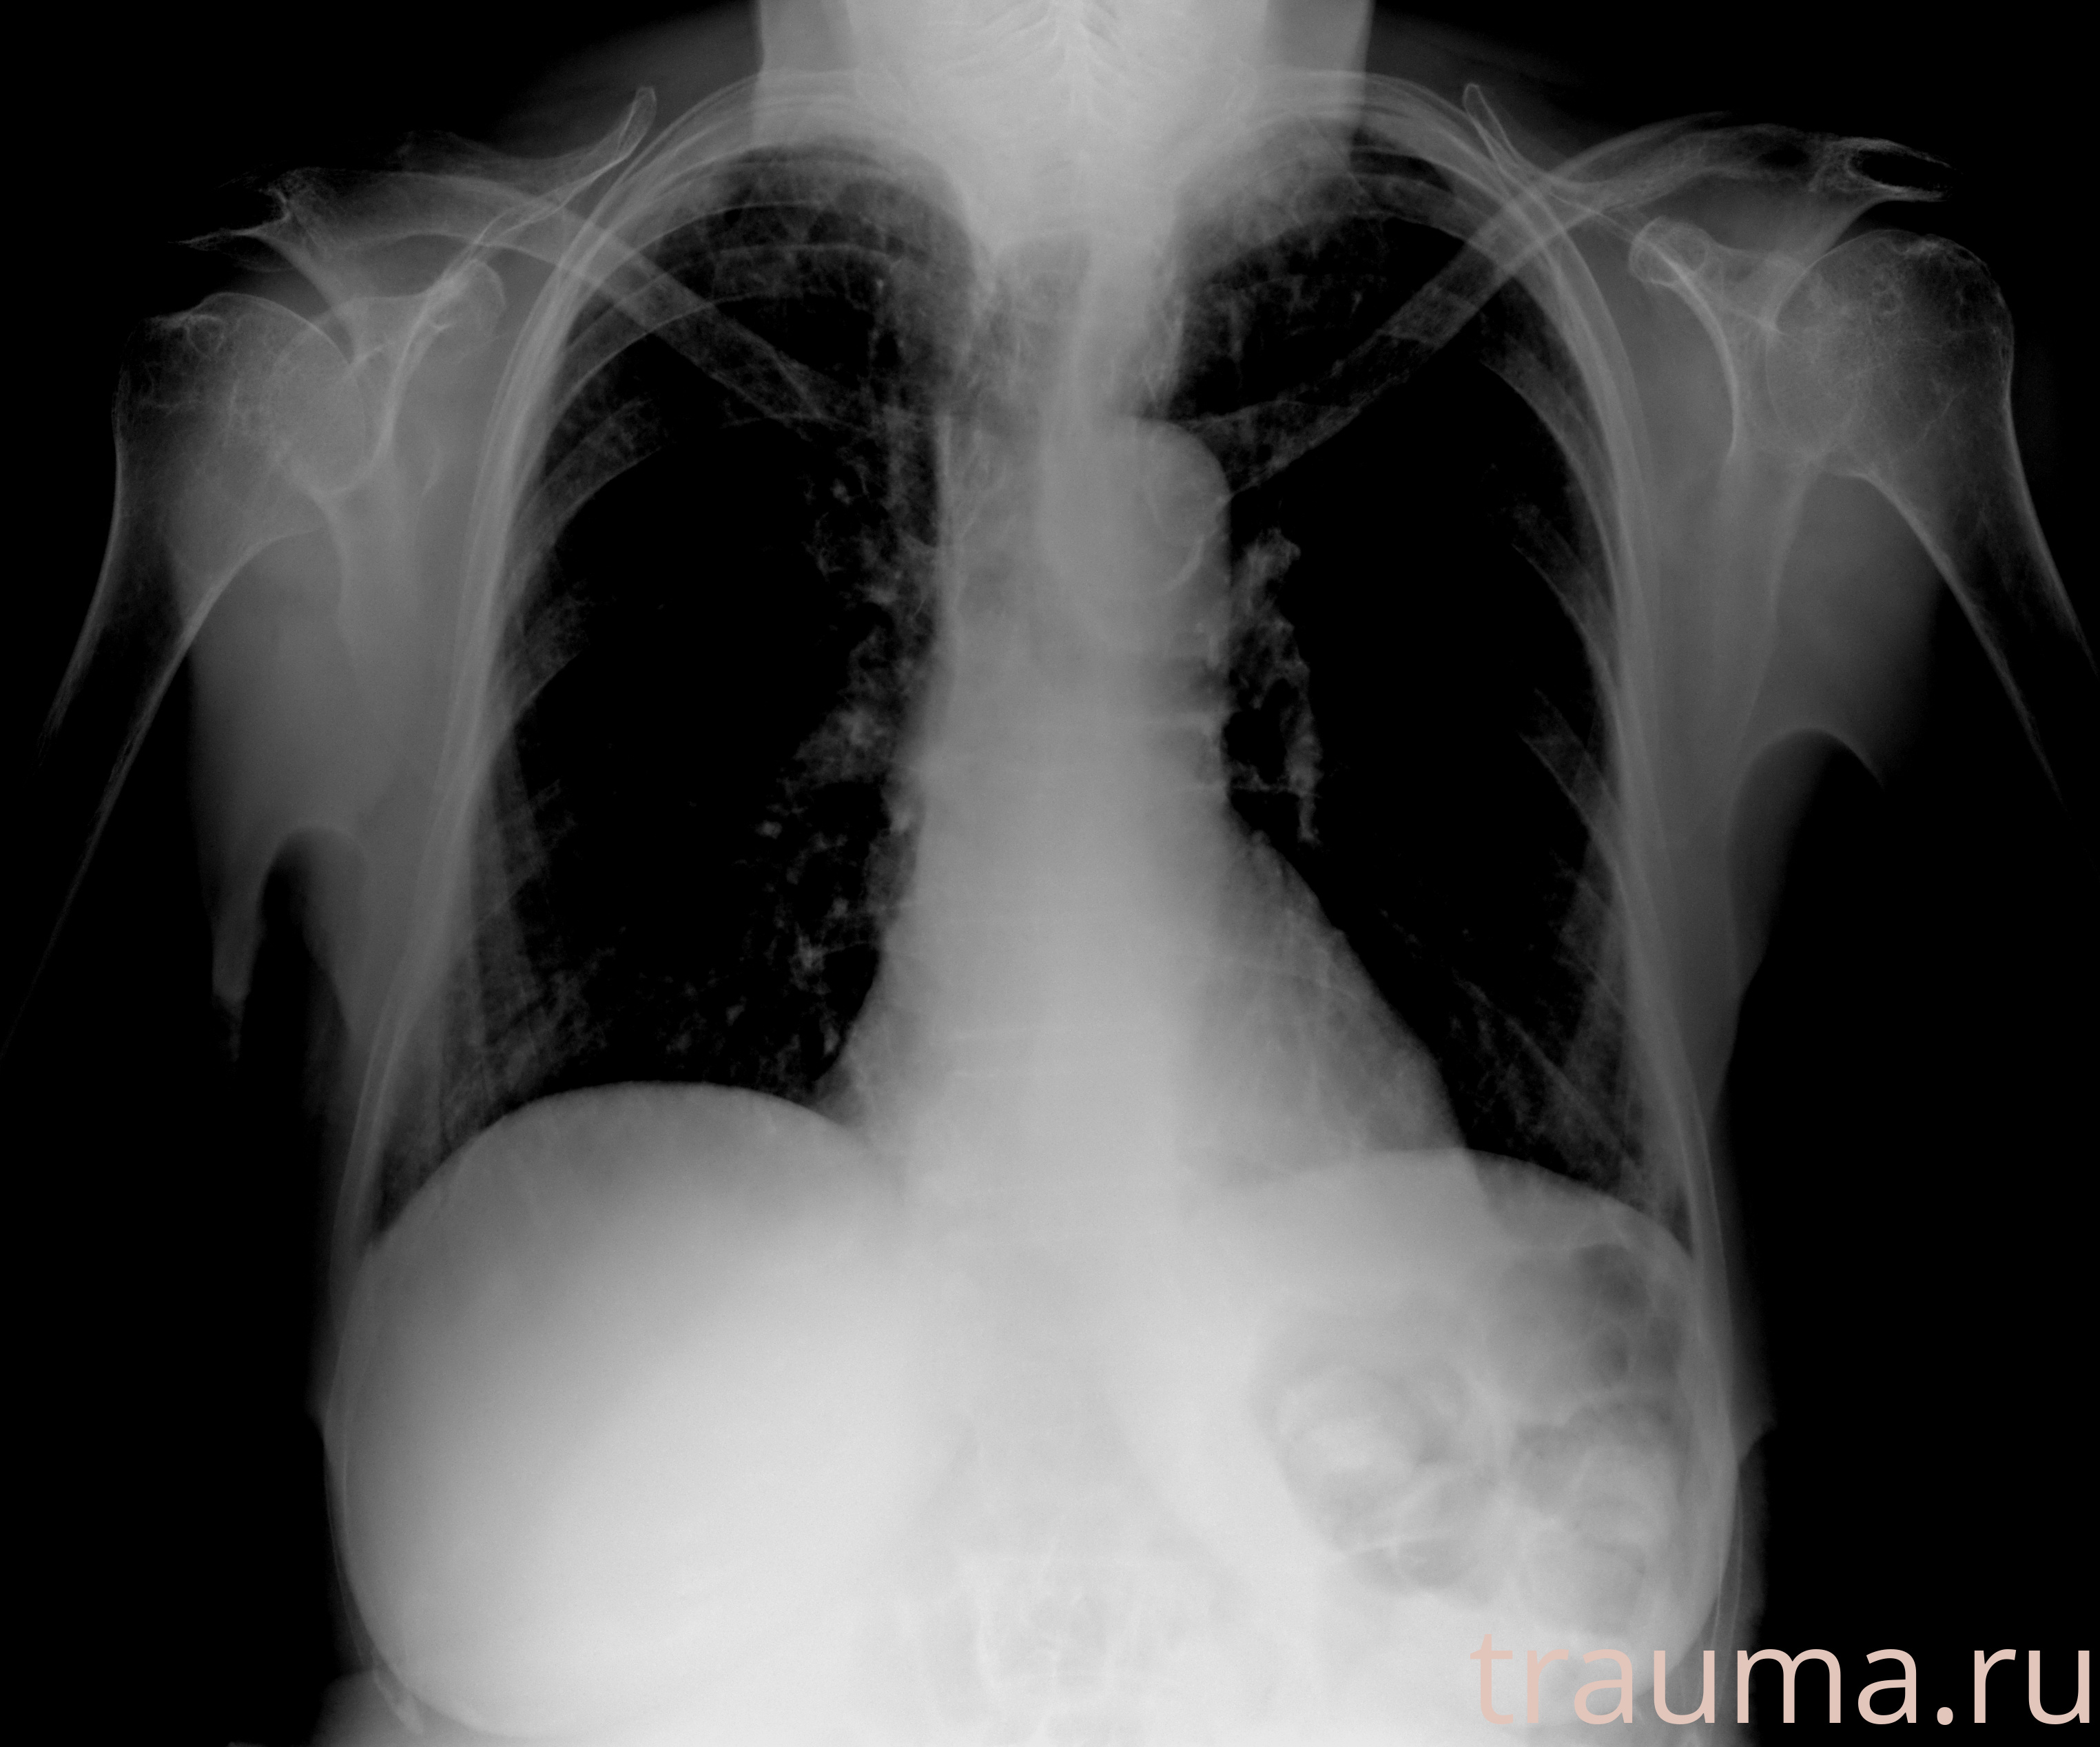

Рентгенограммы

Рентген на дому: по вашему адресу приезжает врач-рентгенолог, травматолог-ортопед с мобильным рентгеновским аппаратом, проводит диагностику травмы или заболевания, делает необходимые рентгенограммы, дает рекомендации по дальнейшему лечению. Получить качественные снимки в домашних условиях возможно благодаря уникальной методике, разработанной МосРентген Центром для института  Склифосовского